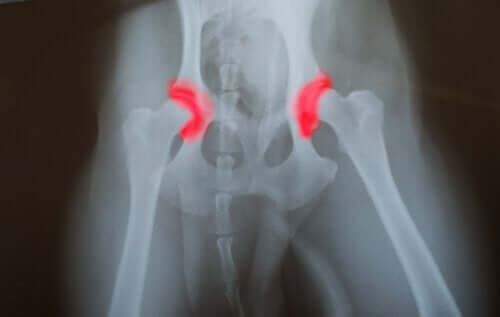

- Hofteledsdysplasi

Sammenlignet med store hunde, der har en ubalanceret kost, havde de, der spiste en afbalanceret kost, færre sygdomme forbundet med overvækst. Hofteledsdysplasi var en af de mest almindelige sygdomme hos store overfodrede hunde.